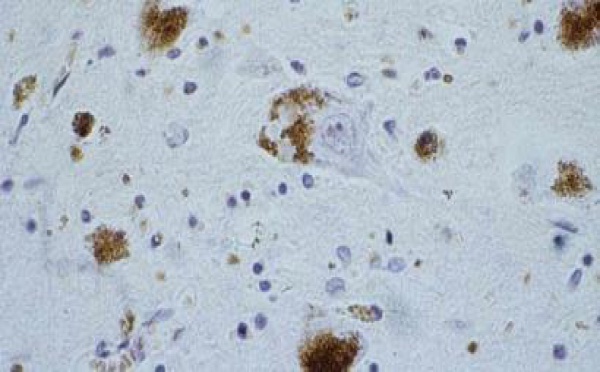

Publication du livre blanc sur la maladie de parkinson

« Le malade de Parkinson est comme l'artiste que l'on voit encore dans les cirques en équilibre sur sa sphère géante. Pour tenir sur la boule, il faut déployer des trésors d'énergie, de courage », résume un patient dans le livre blanc consacré à cette pathologie. Il s’agit d’un recueil qui fait la synthèse des témoignages...